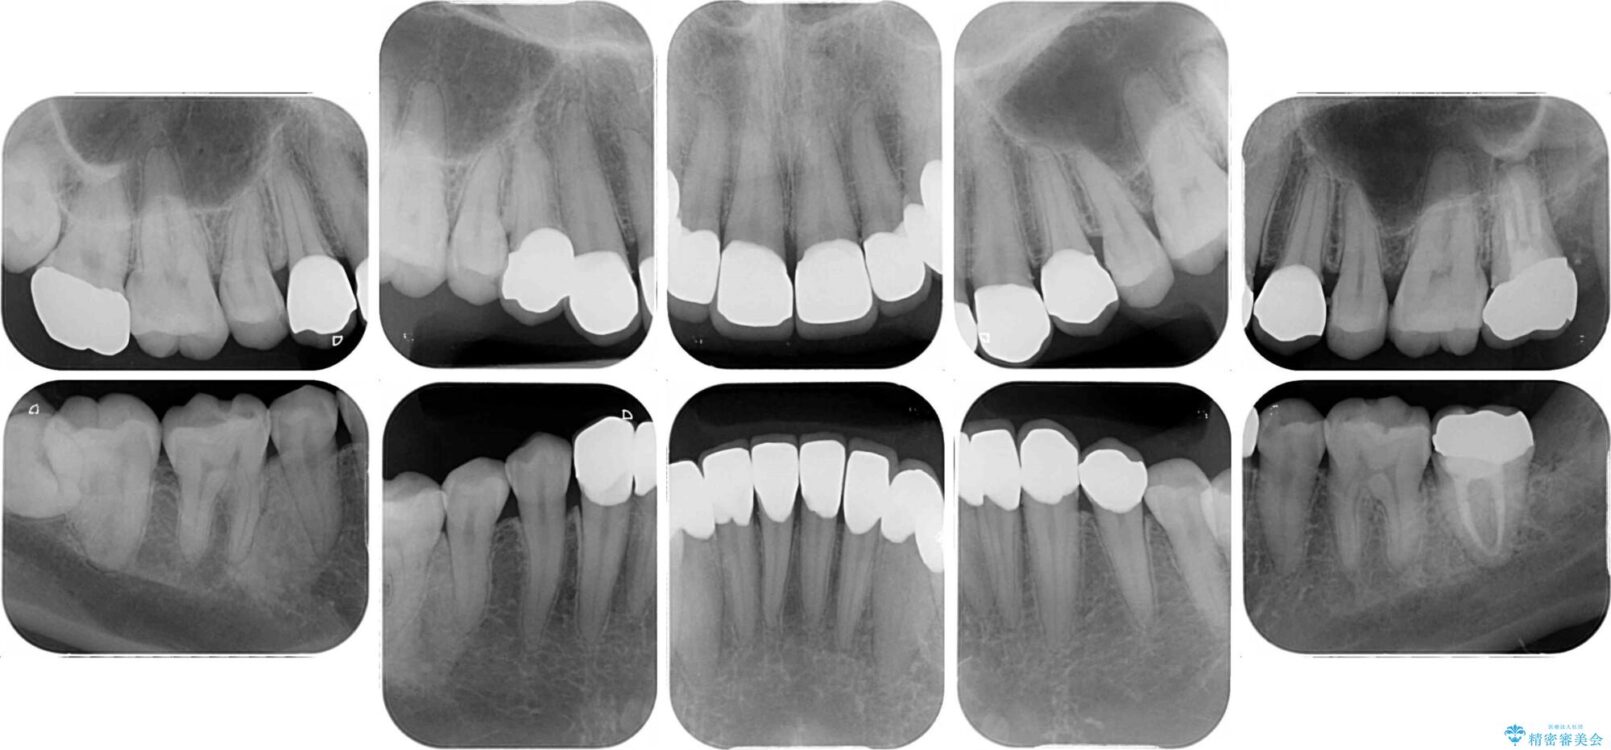

上下前歯や奥歯の虫歯治療を希望して来院された患者様です。

全顎的にむし歯が多く、根管治療の必要な奥歯や、審美的に気になっている前歯を中心にオールセラミッククラウンにて補綴治療を行うこととしました。

治療前

• むし歯だらけの前歯をオールセラミッククラウンできれいに 治療前画像